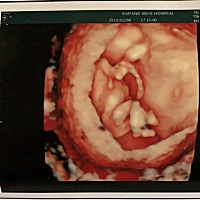

帮忙看看这是中奖了吗……